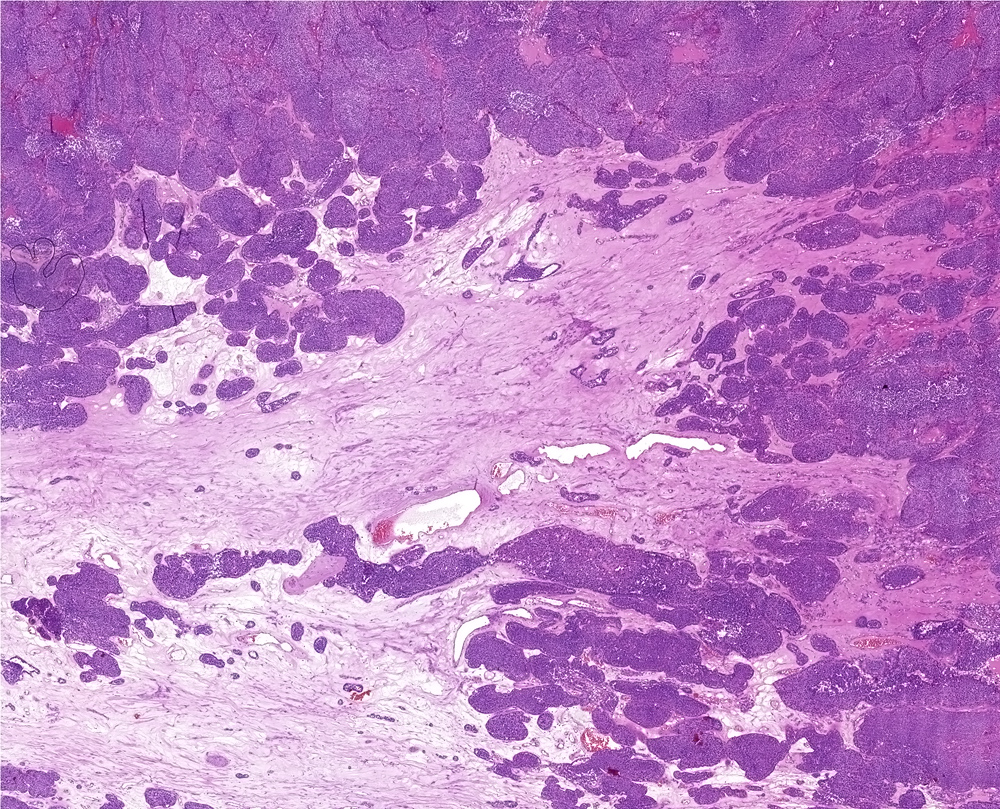

Kidney tumor, 65-year-old female. Tumor located in pole, size 6 x 5.5 x 6.7 cm, yellow color.

Tumor is solid, solid-alveolar with abundant stroma. Cells are relative small with oncocytic scant cytoplasm and irregular nuclei. Islet of cells are surounded by distinct basal membrane. Pseudorosettes are present focally.

Dg: Renal oncocytoma-small cell variant with pseudorosettes